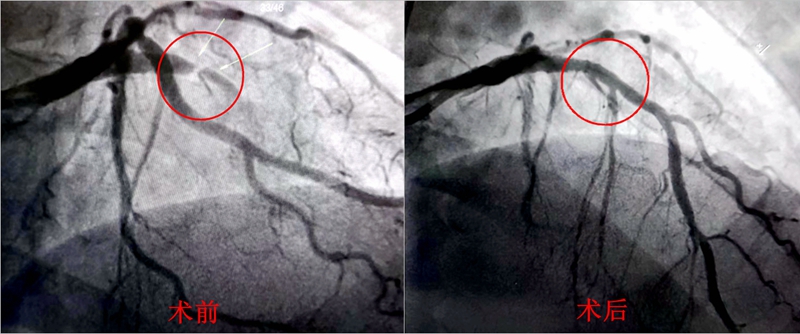

术中造影发现,李叔心脏前降支近段完全闭塞。赖仙辉带领救心团队第一时间植入心脏支架,开通生命通路,成功救下李叔一命。入导管室至导丝通过时间23分钟,DtoW时间55分钟。